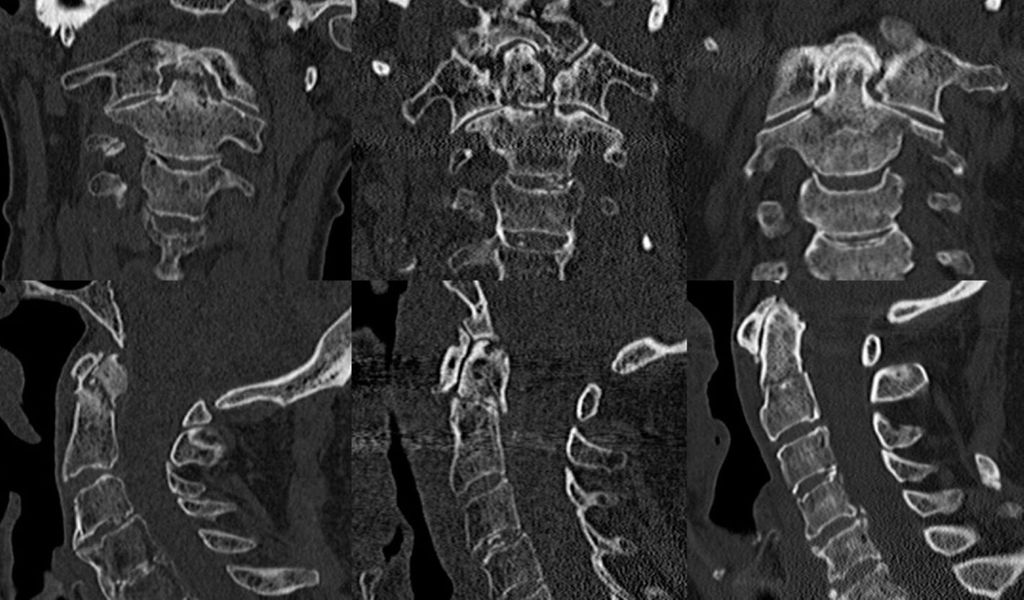

Die posteriore atlantoaxiale Fusion ist zwar invasiver, liefert jedoch bessere chirurgische Ergebnisse hinsichtlich der Frakturheilung und der Notwendigkeit von Revisionen bei höherer Primärstabilität.42 Bei geriatrischen Patienten über 75 Jahre36 wird bei Entscheidung zur Operation eine C1-C2-Arthrodese von dorsal empfohlen.26 Von den posterioren Fusionen am häufigsten durchgeführt werden die 2-Schrauben-Technik nach Magerl und Seeman und die 4-Schrauben-Technik nach Goel und Laheri bzw. Harms und Melcher. Beide erreichen hohe Fusionsraten und gute Stabilität. Zusätzlich zu den Verschraubungen kann auch eine Cerclage nach Gallie/Brooks angelegt werden, um die Stabilität noch zu verbessern (Abb. 2).34

Abb. 2: Post-OP-Röntgenbilder a.p. (obere Reihe) und seitlich (untere Reihe); transartikuläre Verschraubung nach Magerl (links), ventrale Verschraubung mit 2 Schrauben (Mitte) und mit 1 Schraube (rechts oben), Cerclage (rechts unten)